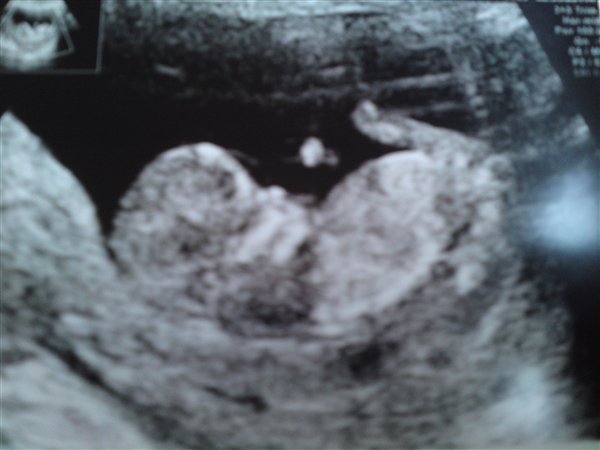

Ja, så er vi hjemme fra NF og fik et FLOT resultat med en risiko på over 20.000!

Alt var så fint så fint og vi fik meget ros! vi hørte hjertelyd, så de 4 hjertekamre osv og det var helt fantastisk

Åh jeg er glad...De var meget imponerede over hvor flot h*n er og der er ingen tvivl om at den lille stump slægter sin far på.. fodboldspiller!!!!!!

Der kommer lige et billede af min skat og lidt nyt af mavsen..

Knus Caroline 11+6